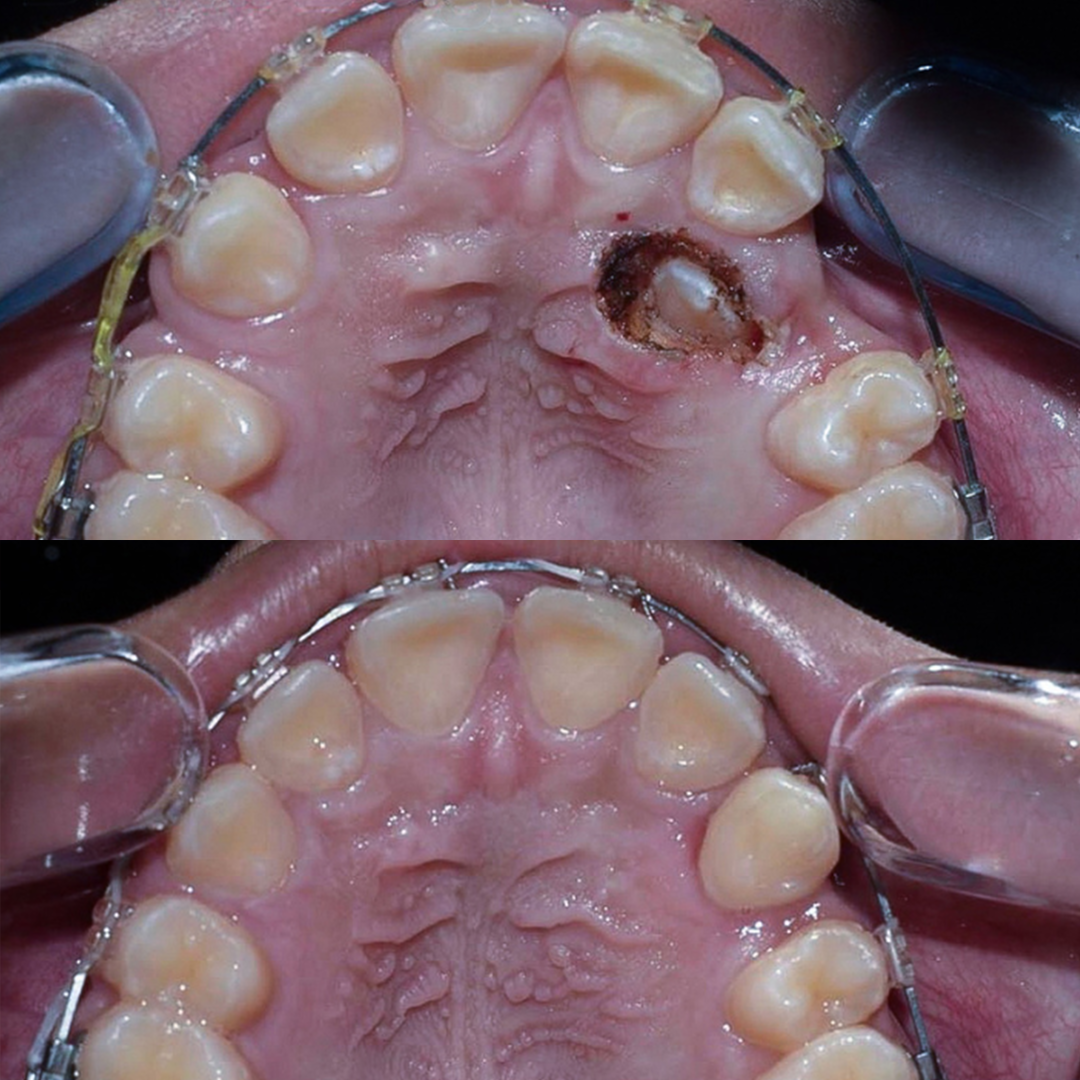

Замена старых композитных реставраций со вторичным кариесом